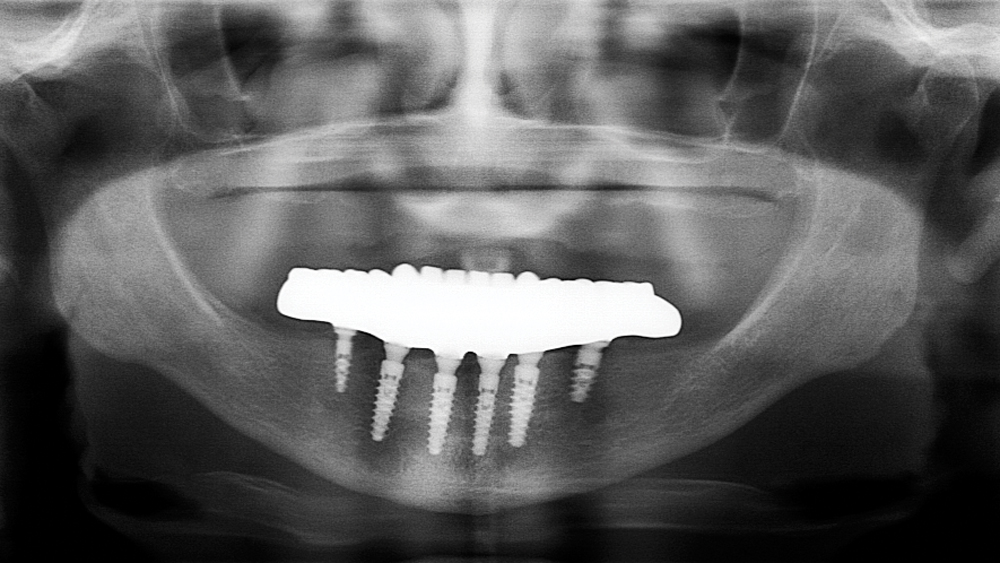

This patient was unhappy with the esthetics of her existing upper denture as well as the discomfort and instability caused by her loose-fitting mandibular partial denture. Although her concerns with the maxillary denture could be addressed with a new, more esthetic appliance, she preferred implant treatment for her mandible, where a fixed solution was needed to adequately restore function, stability and comfort.

Treatment plan:

The patient’s remaining mandibular teeth were extracted followed by immediate implant placement and delivery of a fixed provisional appliance. After integration of the implants, the prosthetic designs for the new upper denture and lower implant restoration were determined in tandem. Ultimately, the dual-arch restorations addressed the functional and esthetic challenges of the case while staying within the financial means of the patient, demonstrating the benefits of a flexible, multifaceted approach to restorative dentistry.